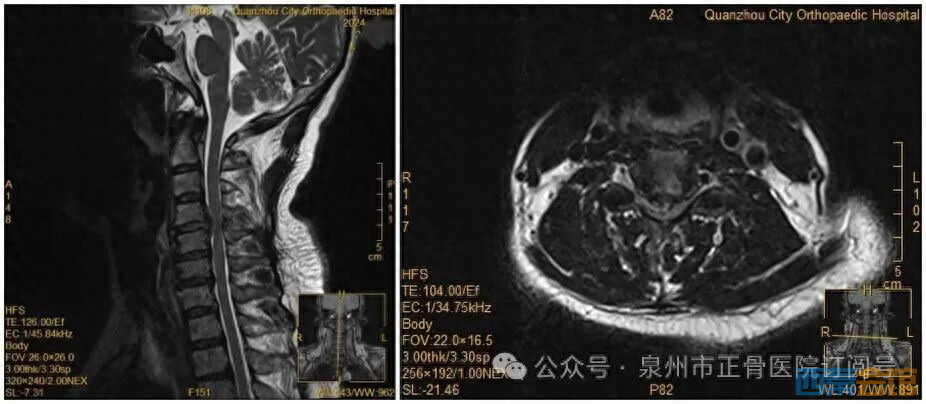

此前,她因手麻、酸痛到医院就诊,被查出颈椎间盘突出症。脊柱二科杨声坪主治医师回忆:“会诊时我们明确告知患者,她的颈椎间盘已经巨大脱出,符合手术指征,建议尽快手术。但她坚持想保守治疗。”

没想到,会诊当晚,王女士翻身拿手机的瞬间,双手突然失去知觉——关键肌肌力降至1级或0级,确诊为瘫痪。“推测是翻身时,脱出的椎间盘突然进一步卡压到脊髓神经,引发了急性症状。”医生表示。

王女士术前MRI